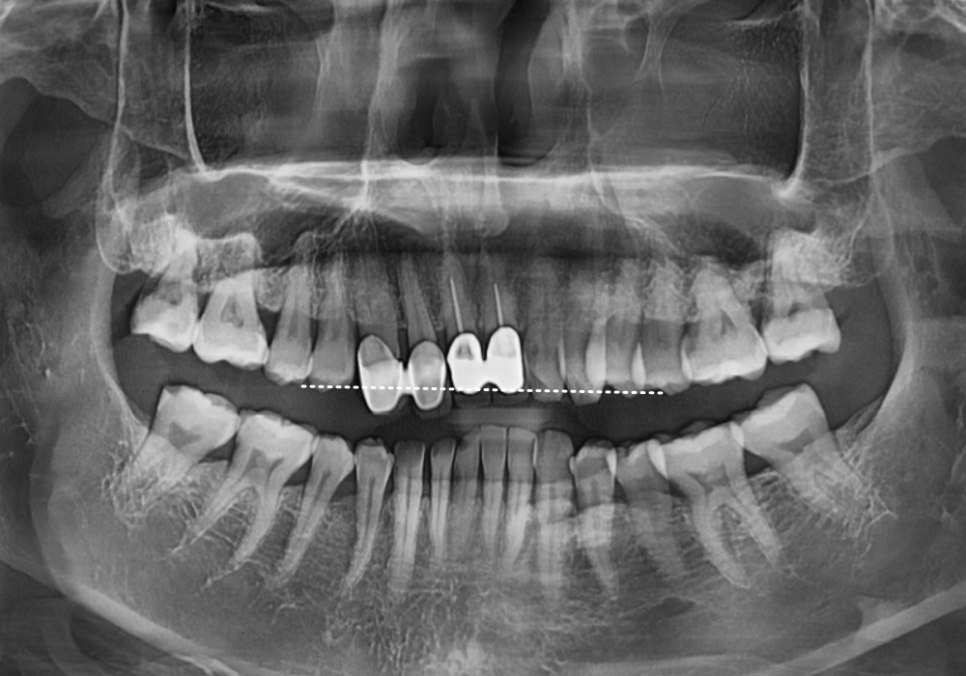

이 환자분은

오래전 위 앞니 4개를

보철로 씌우셨는데,

시간이 흐르면서

심미적으로나 기능적으로

문제가 생긴 상태였습니다.

입안을 자세히 살펴보니

원인은 크게 세 가지였습니다.

유독 길게 제작된 위 앞니가

아랫니를 계속 건드리면서,

아랫니 속살(상아질)이 비칠 만큼

심하게 마모되어 있었습니다.

아랫니가 닳아 키가 작아지다 보니,

상대적으로 윗니는 더 들쑥날쑥하고

삐뚤어 보일 수밖에 없었죠.

잇몸이 내려가면서

뿌리가 드러나보이고,

보철 안쪽의 금속 테두리가

까맣게 보였습니다.

무엇보다 "씹을 때 욱신거린다"는

통증을 호소하셨는데,

정밀 검사 결과 ,

과거 신경치료가 제대로 마무리되지 않아

내부에 염증이 생겨 있었습니다.

230215

결국 기존 재료를 모두 제거하고

다시 치료하는 '재신경치료'가

시급한 상황이었습니다.